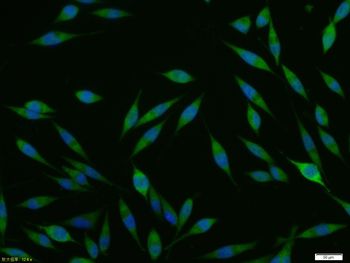

FC, ICC, WB

应用稀释比例:WB=1:500-2000, ICC/IF=1:100-500, Flow-Cyt=2ug/Test